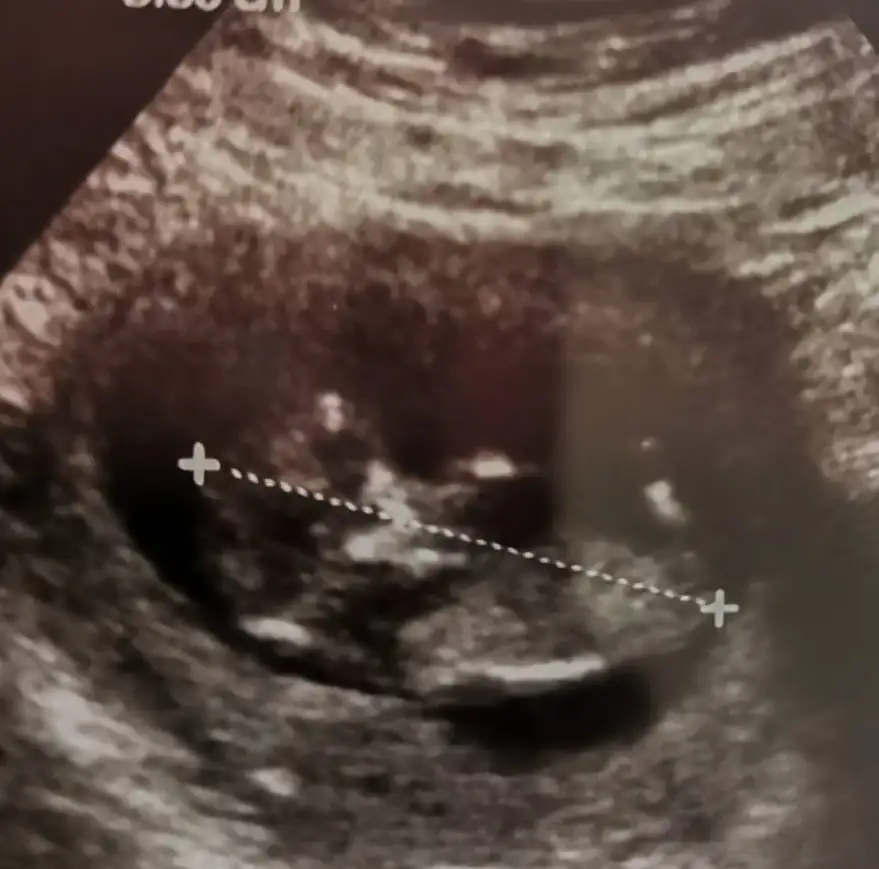

İkra meyra rica etsem bebeğimin nubuna bakabilir misiniz 12 haftalık

• image.webp

25 KB · Görüntüleme: 59